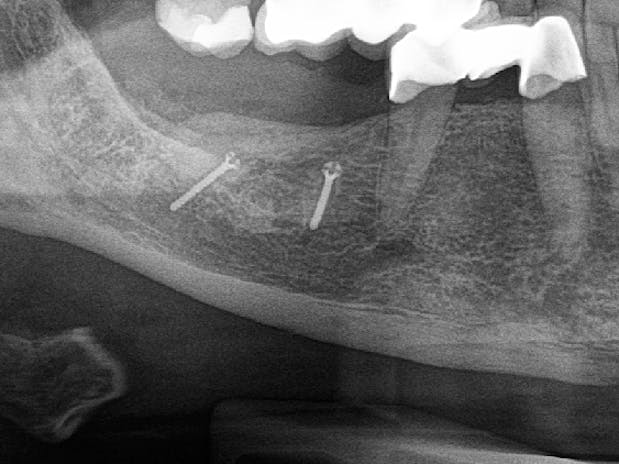

Bei größeren Knochendefekten ist mitunter die Entnahme von passenden Knochentransplantaten, meist aus dem Kieferbereich, erforderlich. In Fällen hochgradigen Knochenabbaus ganzer Kiefer greifen wir bei Bedarf auf Transplantate vom Beckenkamm zurück.